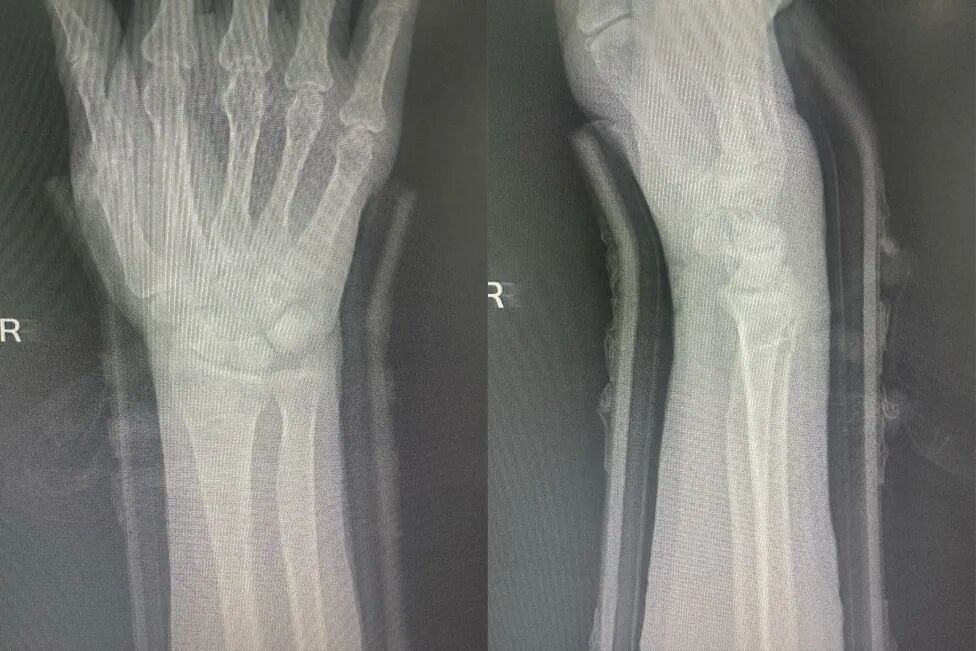

图片

复位后

治疗后,赵主任详细指导患者进行手指抓握、肩肘活动等功能锻炼,并叮嘱定期复查调整夹板松紧。一周后复查,患者肿胀消退,X光显示骨折对位良好。